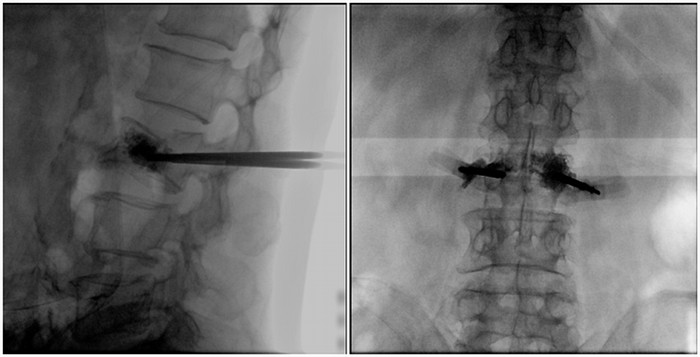

术中切口5毫米,在大平板C臂机的透视指引下,确定了进针的方向及进针的深度。经椎弓根向椎体置管,建立通道,插入骨扩张器(球囊)。球囊扩张恢复椎体高度,并在椎体内形成空腔,确定骨水泥的注入剂量,并注入骨水泥观察其扩散情况。

大平板C臂机临床图像

市面上主流的小C大多采用21CM×21CM的平板或者影像增强器,成像范围较小,一般可成像3.5节腰椎,确定伤椎可能需要进行多次拍摄。普爱医疗大平板C臂机采用30CM×30CM的平板探测器,一般可一次性成像5节腰椎,呈现更广阔的视野。使医生一次性全面地观察到伤椎及周围椎体情况,使得手术效率更高、更准确。如果您想采购,或了解这款大平板C臂机技术参数,欢迎咨询400-025-6366。